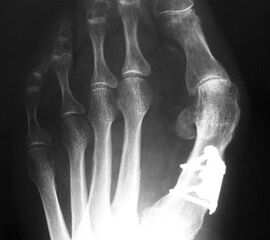

Die dorsoplantaren Röntgenaufnahmen zeigen eine Open-wedge Technik mit der normalerweise ein erhöhter intermetatarsaler Winkel gut zu korrigieren ist (Abbildung 3). Die Wirksamkeit einer Basisosteotomie ist umso größer, je proximaler diese durchgeführt wird. Je weiter distal die Osteotomie, umso geringer die Korrektur. Auf den postoperativen Bildern ist der distal unverändert große Abstand zwischen Metatarsale I und Metatarsale II erkennbar, bei gleichzeitiger Subluxation des Großzehengrundgelenks und dezentrierten Sesambeinen. Darüber hinaus finden sich initiale degenerative Veränderungen im Großzehengrundgelenk. Klinisch bestand eine hohe Weichteilspannung, bei verkürzter Extensor- und Flexor hallucis longus Sehne.  Daher wurde ein verkürzendes Verfahren zur Revision gewählt (Abbildung 4). Die Lapidusarthrodese stellt ein sehr zuverlässiges Verfahren zur Behandlung von Hallux valgus Rezidiven dar 9. Die Fusion des Tarsometatarsale-I-Gelenks kombiniert Stabilität mit einem hohen Korrekturpotenzial. Aufgrund der verfahrensimmanenten Verkürzung des ersten Strahls und der in diesem Fall bereits präoperativ vorhandenen Transfermetatarsalgie wurde die Entscheidung für eine verkürzte Weil-Osteotomie am zweiten bis fünften Strahl gefällt. Die Kombination beider Verfahren führte zu einem homogenen Metatarsale-Index und zu einer gleichmäßigen plantaren Druckverteilung 10. Die Hallux valgus interphalangeus Fehlstellung wurde mit einer Akin-Osteotomie korrigiert.